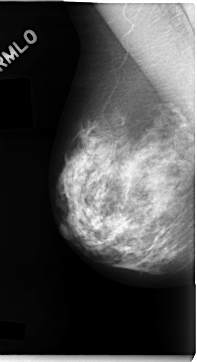

C_0062_1.RIGHT_MLO

RIGHT_CC LINES 4712 PIXELS_PER_LINE 2488 BITS_PER_PIXEL 12 RESOLUTION 50 NON_OVERLAY

RIGHT_MLO LINES 4696 PIXELS_PER_LINE 2552 BITS_PER_PIXEL 12 RESOLUTION 50 NON_OVERLAY